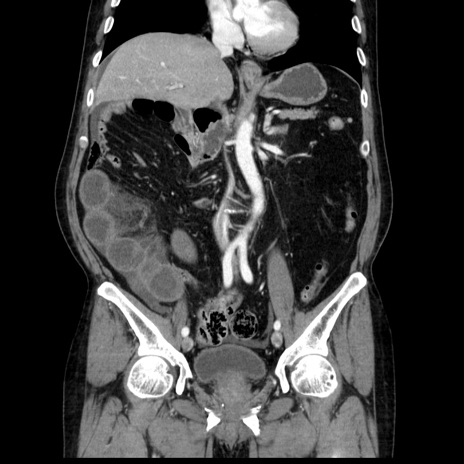

症例30(冠状断像)

【症例】80歳代男性

【主訴】臍周囲痛

【現病歴】約6時間前から臍下部痛が出現。次第に腹部膨隆・背部痛も生じてきたため来院。背部痛の場所は変化しない。

【身体所見】意識清明、BT 36.3℃、BP  131/87mmHg、P 87bpm、SpO2 100%(RA)、臍周囲自発痛・圧痛あり、反跳痛なし、自発痛部位に一致して板状硬あり、腹部膨隆、腸雑音減弱、CVA tenderness両側陰性。

【データ】WBC 19600、CRP 0.33